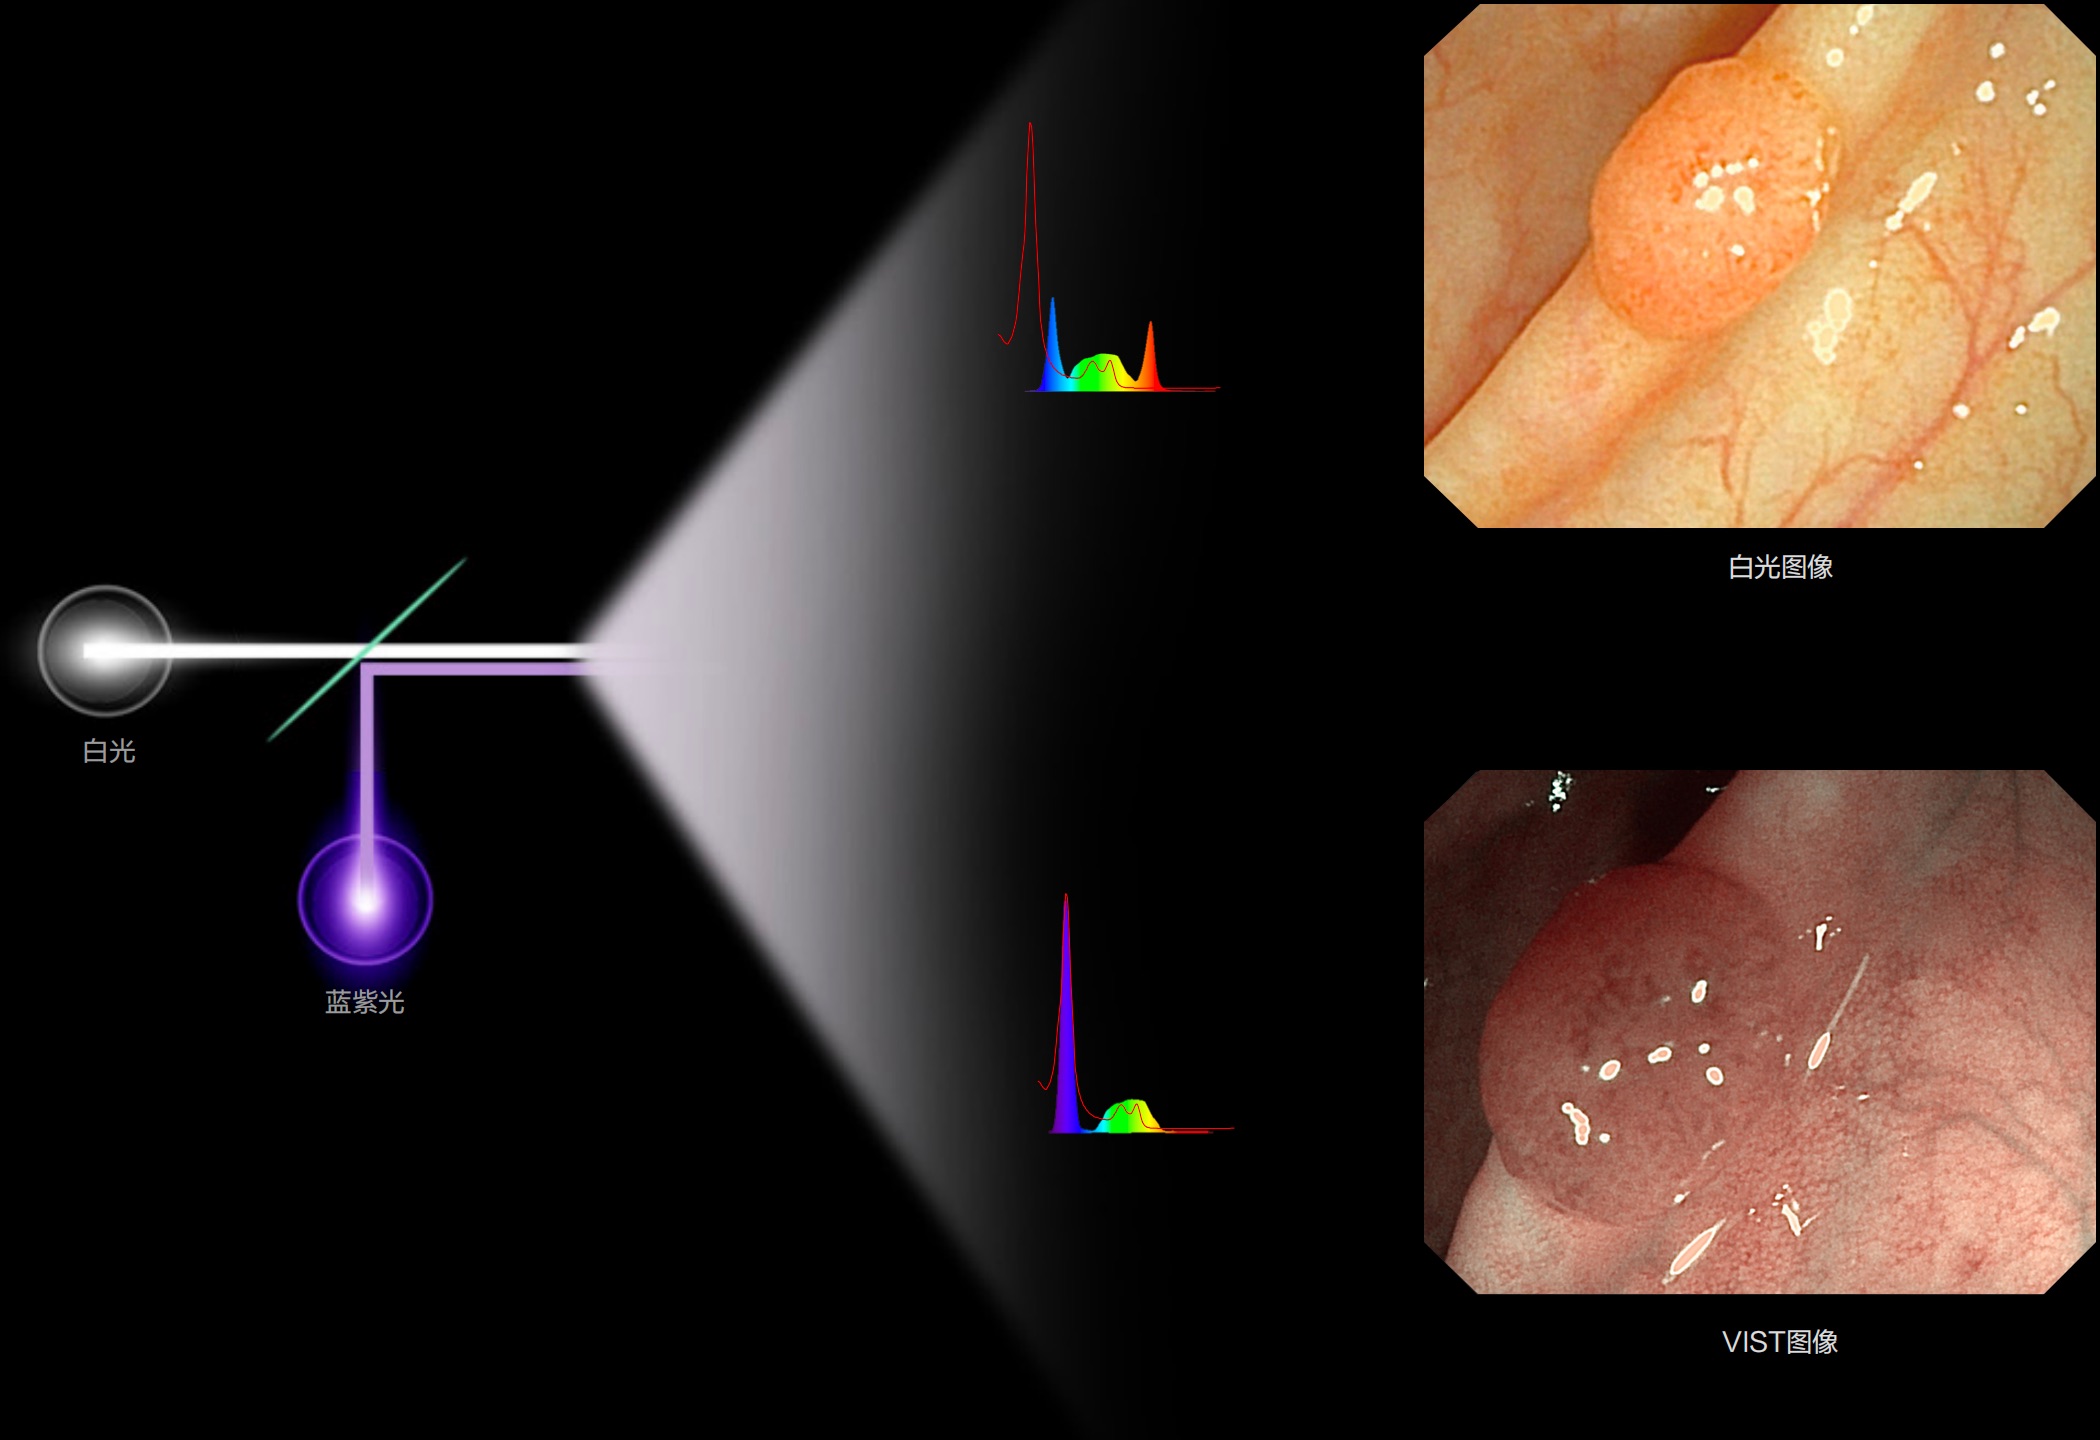

(Spectral Focused lmaging, SFI)

能够凸显黏膜浅层和中层血管轮廓,适用于中、远景观察下的病灶识别和早癌筛查。

照明光谱

光谱提取

光谱提取能量汇聚

RGB图像重建

染色模式显示

白光图像

(Versatile Intelligent Staining Technology)

能够凸显黏膜浅层血管轮廓和黏膜表面微结构,适用于中、近景观察下的早癌精确诊断。